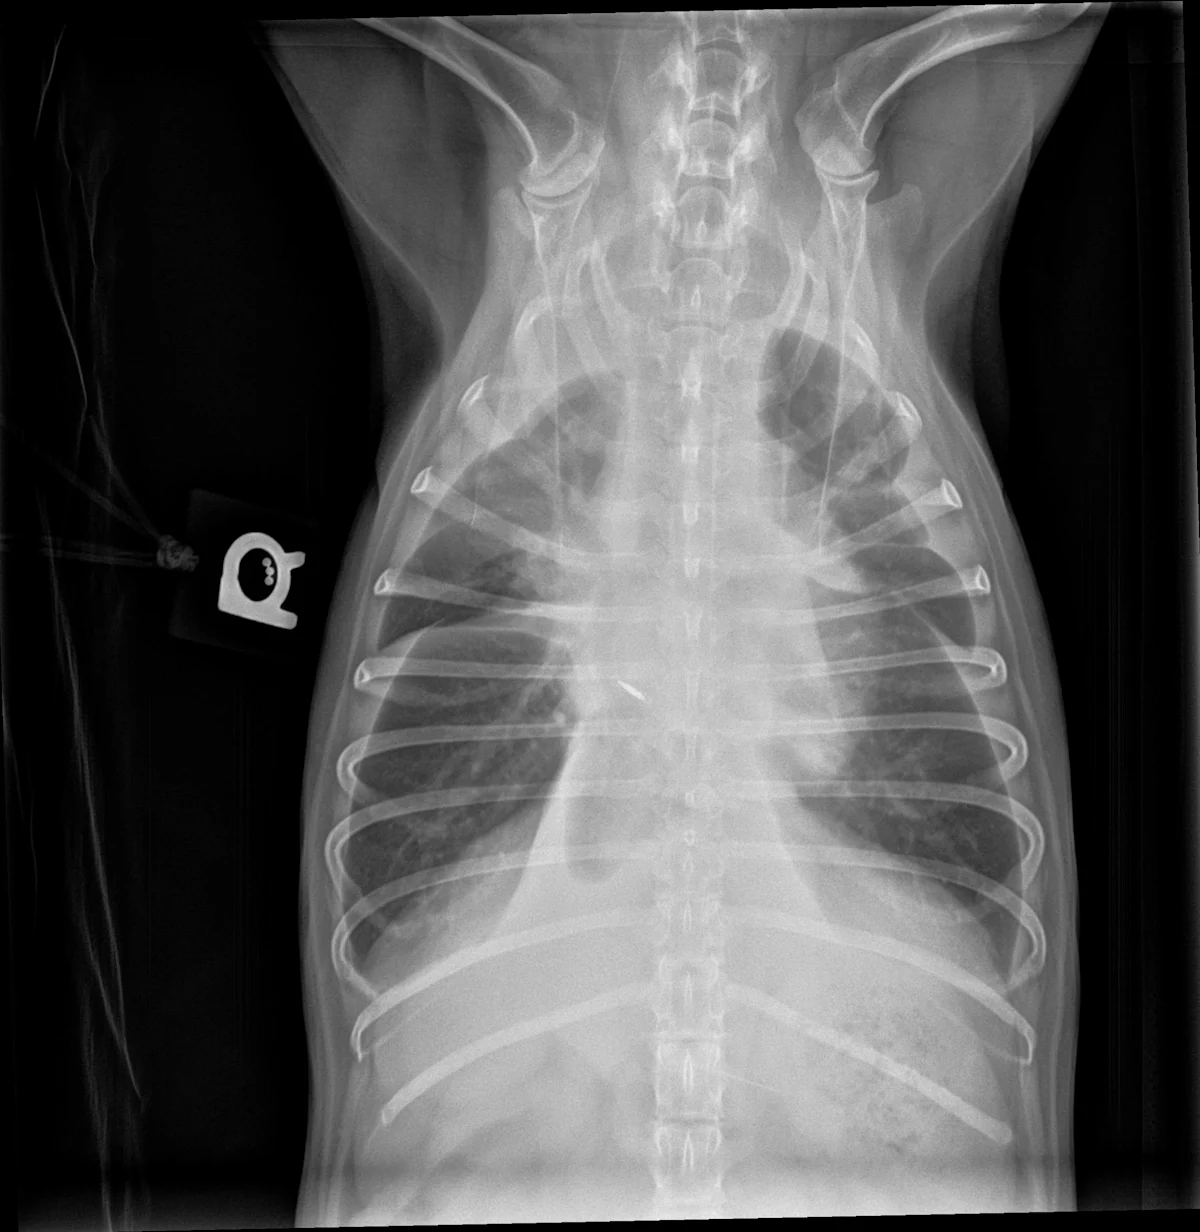

Pleural effusion can be easily identified on radiographs (Figures 1 and 2) and ultrasound (Figure 3). In patients with respiratory distress, oxygen and sedation should be administered before standard aseptic, often ultrasound-guided, thoracocentesis is performed. Removal and collection of fluid can quickly improve oxygenation and ventilation and allow clinical investigation to determine the cause of effusion.

Right lateral radiograph of a dog with moderate to severe pleural effusion